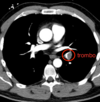

TC en TEP

Es diagnóstica, nos permite ver el trombo

TEP

4 = trombo